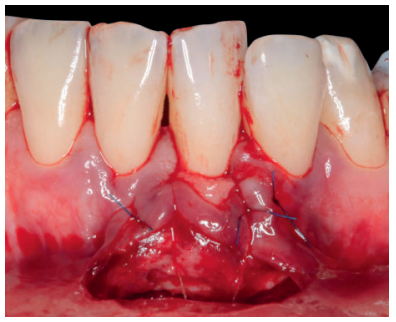

Se realizó control a la semana de la intervención (Figura 4) y tras 15 días se retiró la sutura, observando la revascularización del injerto y la epitelización del área cruenta apical al sobre (Figura 5). Se realizó seguimiento al mes (Figura 6), a los 3 meses (Figura 7) y al año y medio del procedimiento (Figura 8).

Previamente a la intervención, la paciente se enjuagó durante un minuto con un colutorio de clorhexidina. La técnica quirúrgica comenzó con la preparación del lecho receptor, se realizaron incisiones intrasulculares a nivel cervical hasta la línea ángulo de todos los dientes del frente antero-inferior (33-43), desinsertando la base de la papila sin seccionarla con la ayuda de instrumentos de tunelización. Posteriormente se realizó una incisión en el fondo de vestíbulo (Figura 11). A continuación, se obtuvo un injerto de tejido conectivo del paladar introduciéndolo en el lecho receptor, siendo todas las suturas realizadas de la misma manera que en el caso clínico 1, usando tanto material reabsorbible como no reabsorbible de 5/0 y 6/0 ceros (Figura 12).

El control a la semana (Figura 13) presentaba inflamación moderada y a las 2 semanas (Figura 14) se retiraron los puntos de sutura. La paciente acudió a los 4 meses (Figura 15) y al año (Figura 16) a visitas de revisión, donde se apreció una buena banda de tejido queratinizado y una pequeña cicatriz.